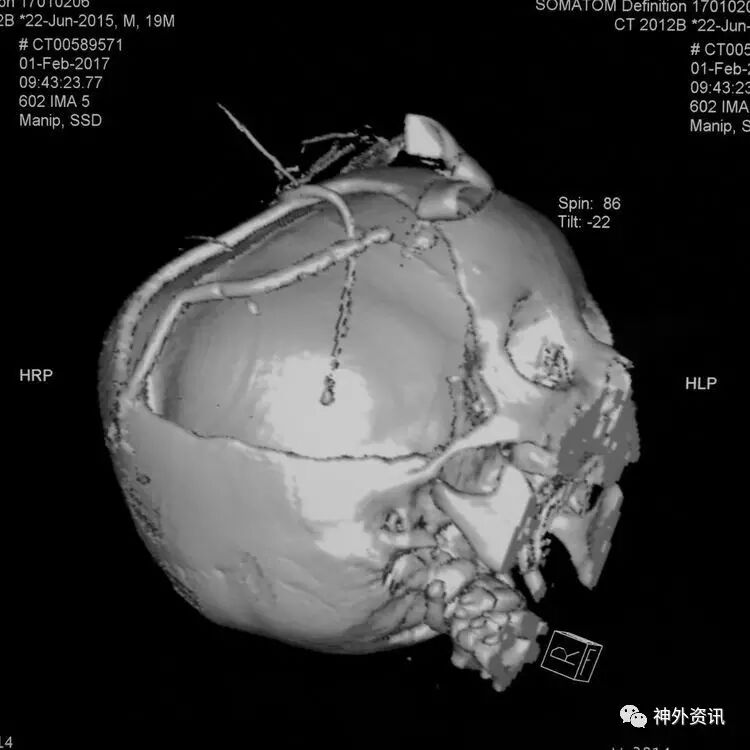

急诊在全麻下行右额颞顶开颅去骨瓣减压+脑室外引流+ICP探头置入术:

术后移动CT结果示中线移位较术前减轻,顶枕部蛛网膜下腔出血: